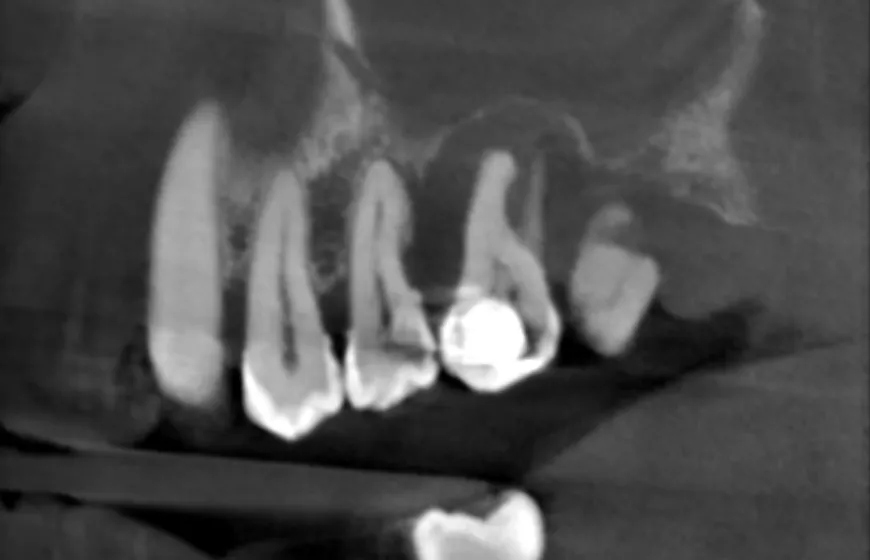

- Opracowanie i dezynfekcja kanałów korzeniowych: Za pomocą specjalnych narzędzi dokładnie oczyszczamy kanały z resztek miazgi i bakterii.

- Wypełnienie kanałów: Po dokładnym oczyszczeniu i osuszeniu, kanały są szczelnie wypełniane specjalnym materiałem, najczęściej gutaperką, aby zapobiec ponownej infekcji.